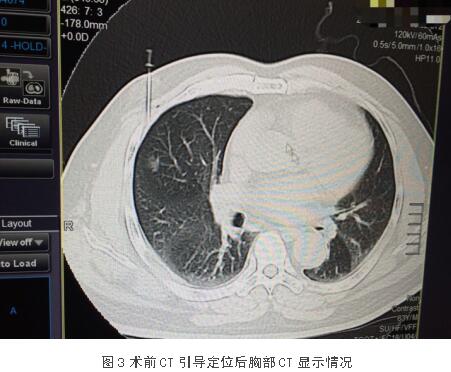

患者李某,男,63岁,发现肺部结节3月余。入住市中心医院后完善相关检查检验,并结合患者症状及体征,经检查患者无明显手术禁忌,符合手术指征,积极行术前准备,考虑结节较小且恶性程度可能性大。在杨斌主任医师与李卫国副主任医师的细致讨论下,交换意见后明确此类微小的肺结节于腔镜下较难寻找,加之CT片的解剖位置会发生一定变化(右肺不能膨起),难以利用触感去确定其具体位置及边界,尤其是质地与肺组织相近的占位,故决定术前1小时给予CT穿刺定位,明确占位方位及所需切割大致边界,以便后续手术安全且迅速实施。

在杨斌主任医师、李卫国副主任医师以及麻醉医师的默契配合下,该患者手术过程顺利,术后安返病房。术后病理诊断:微小浸润性腺癌。目前患者恢复良好,已出院。